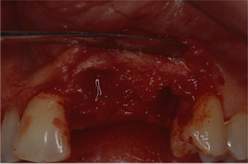

Fig. 1

Epulide fibromatosa in regione 22 e 23 .

Fig. 2 e Fig. 3

Il sondino parodontale rileva una tasca si 14 mm., a dimostrazione dell'inserzione profonda nel parodonto profondo, oltre che nel legamento parodontale.

Fig. 4

Si vede bene il coinvolgimento massivo dei 21, 22 e 23 .